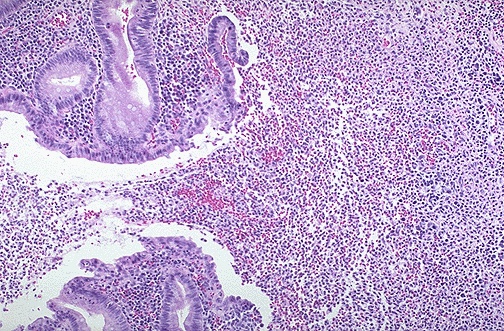

Image 2.4

The medium power microscopic appearance of the appendix removed at surgery is shown here.